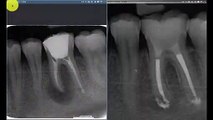

wsr ist die abkürzung für wurzelspitzenresektion. ein chirurgischer eingriff, der in der regel nichts bringt https://www.youtube.com/channel/UCtfezrProo8WbGBSwaEOMIA/search?query=wsr